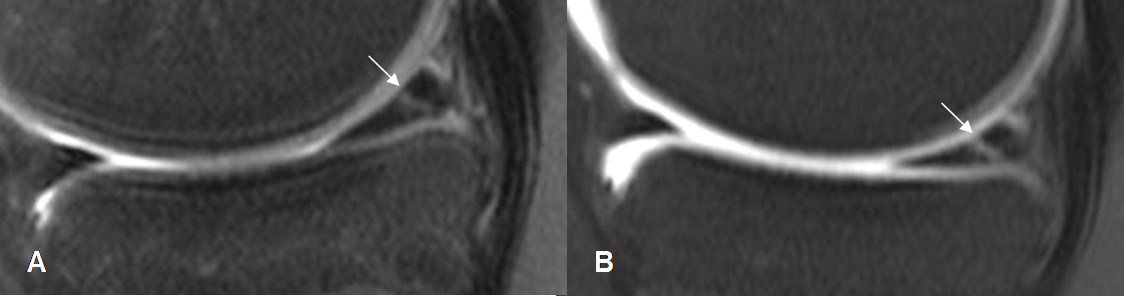

Fig 70. Ruptura meniscal.

A: RM sagital en T1 y B: RM sagital en T2. Imagen en sentido oblicuo, hiperintensa en ambas secuencias, que se comunica con las superficies articulares superior e inferior, por ruptura.